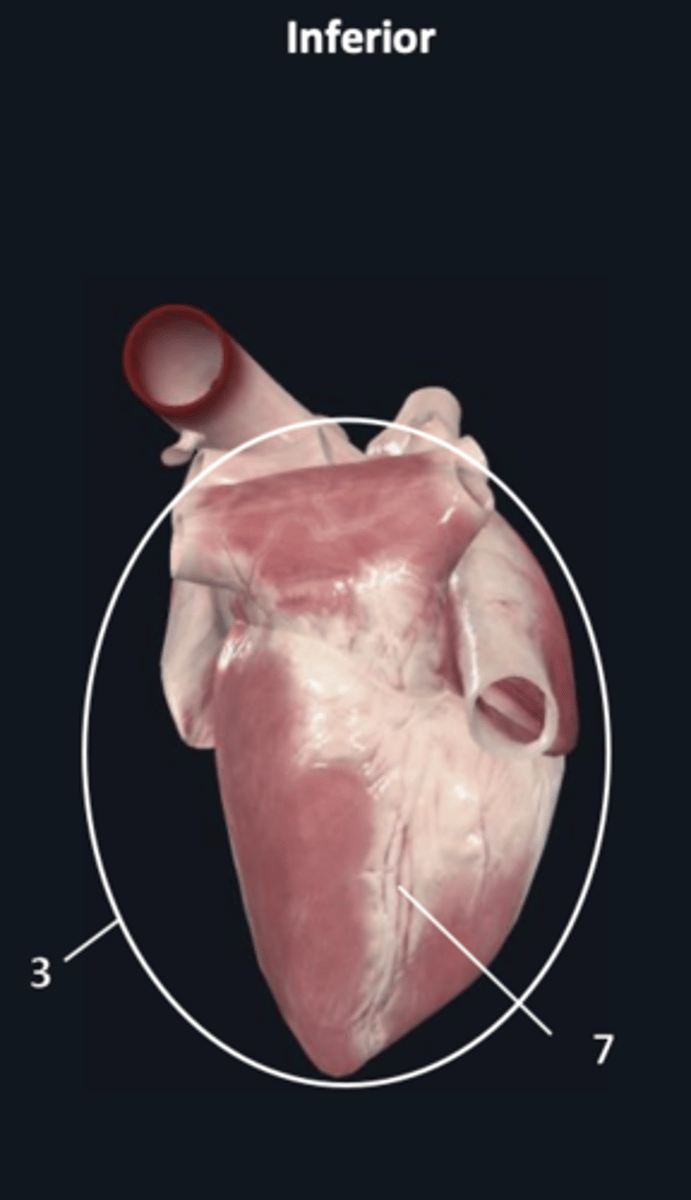

apex

1

diaphragmatic surface

3

posterior interventricular sulcus

7